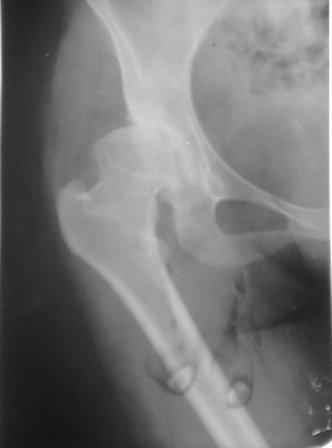

Типичная концовка проигнорированного диспластического состояния сустава. Дисплазия тазобедренного сустава часто встречающаяся патология у жителей Центральной Азии вследствие тугого пеленания в детстве. Традиционно ребенок находится в течение дня в так называемой кроватке "бешик", удобной в быту, но она впоследствии приводит к недоразвитию тазобедренного сустава.

У женщин болезнь клинически проявляется после беременности болями в суставе. Но во время беременности из-за невозможности рентген обследования проблема игнорируется, и упускается время. После беременности симптомы исчезают, и проявляются во время следующей беременности или после увеличения веса.

Это первые признаки начала деструкции сустава, и возможно, аналгетики помогут для купирования болей, но в течение очень короткого времени от сустава ничего не останется, и в дальнейшем останется только артропластика.

При более сохранном суставе от дальнейшего разрушения можно было бы сохранить только периориентацией нагрузки на сустав - Периацетабулярной Остеотомией .

Данный сустав в начальной стадии разрушения, но все-таки я бы сделал обзорный таз и отдельные снимки сустава в 30 градусной абдукции и аддукции. Также снимки с внутренней и наружной ротацией для оценки состояния головки бедра.